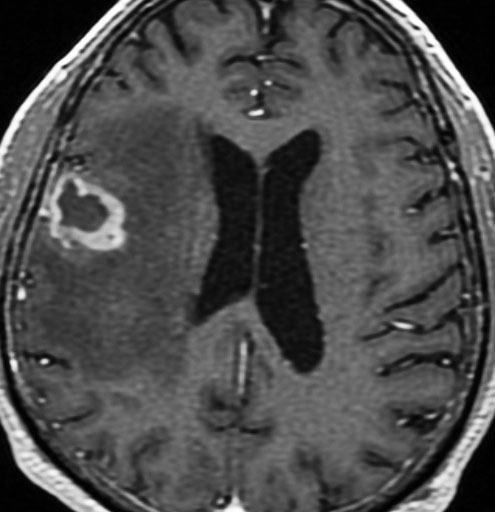

手術後の脳浮腫の改善

手術で放射線壊死巣を摘出してから1月半後のMRIです。放射線壊死が摘出されて,脳浮腫もかなり改善しました。同時に右麻痺もよくなってきました。

この例では,アバスチンを投与するという選択肢もあったのですが,医療費が高額で患者さんが経済的に耐えられません。